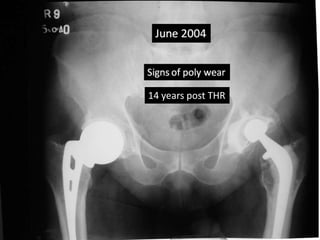

• Advised revision of cup due to poly wear 2005

14 years post THR

Case summary •36 yrs Male had Bilateral AVN hips • AMP done in 1988 rt side at the age of 36 yrs • Triad - cemented THR was done on left side in 1990 at the age of 38 yrs. • Advised revision of cup due to poly wear 2005 • Met with Road traffic accident in June 2007.